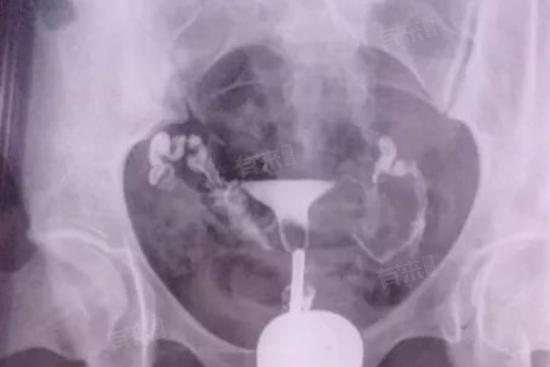

- 输卵管造影的检查方式也对费用有影响。传统的X线输卵管造影,费用一般在500-1000元。这种检查方式通过向宫腔及输卵管注入造影剂,利用X线透视及摄片,观察造影剂在输卵管及盆腔内的显影情况。而超声下输卵管造影费用在800-1500元。超声造影是利用超声造影剂增强回声效果,实时动态观察输卵管的通畅性。